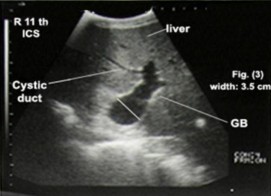

正常牛胆囊超声图

牛用B超机超声检查上,胆囊具有典型的充满液体的囊泡图像,因此在超声检查上几乎是无回声的,周围有薄薄的白色边缘。 胆囊位于肝脏的内脏表面。 根据饱满程度,胆囊延伸超出腹侧肝脏边缘,使其直接邻近腹壁, 胆囊的大小差异很大。通过沿着胆囊颈部和胆囊管,通常可以识别肝总管。

胆囊在肝脏腹内侧成像,并与颅十二指肠密切相关,它表现为黑色囊肿(充满液体的囊泡),管腔无回声,边缘有细小的回声,呈梨形。胆囊管在纵向截面上成像为细长的无回声结构,具有回声壁,在横截面上成像为管状无回声结构,在截面上具有回声壁(看下图)。